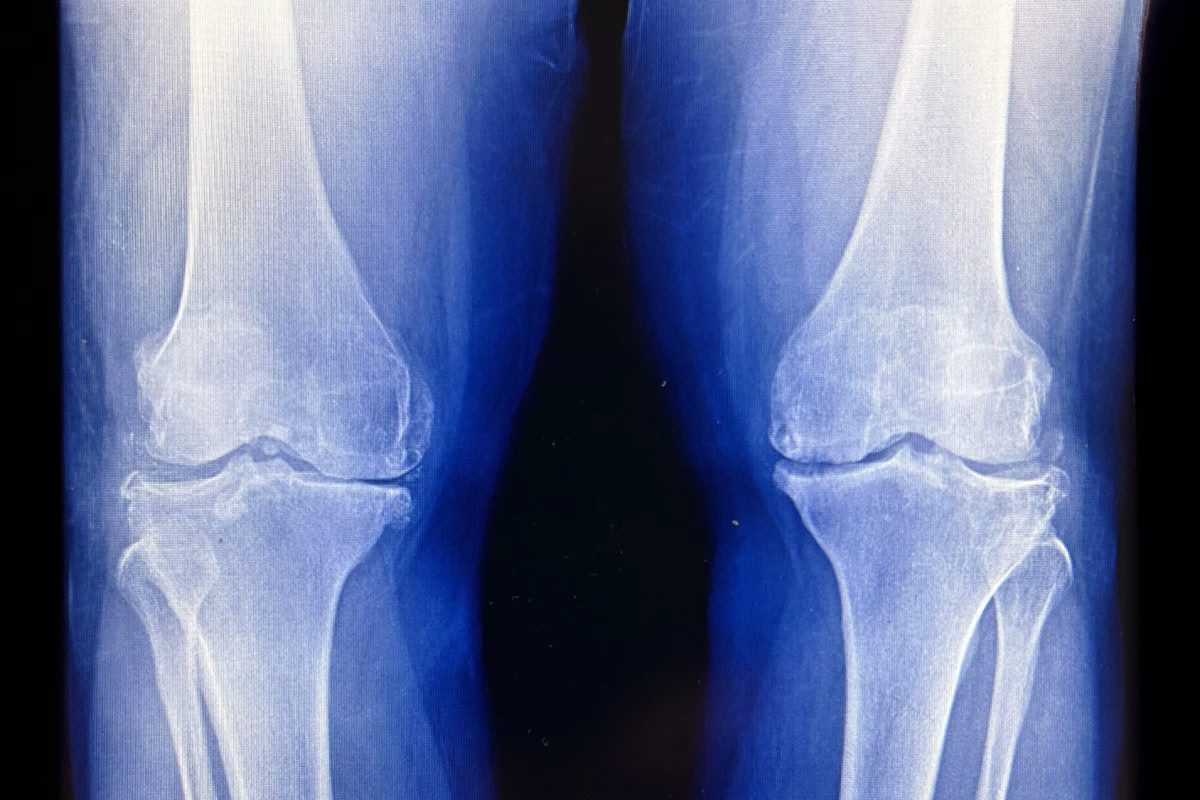

Группа корейских ученых привлекла 114 добровольцев с первичным остеартрозом коленного сустава. Диагноз всем им ставился по рентгеновским снимкам и наличию существенной боли при ходьбе. Участников разбили на три группы: первой колени облучали сверхмалыми дозами радиации (шесть сеансов по 0,05 грея), второй — малыми (то же число сеансов по 0,5 грея), третью не облучали ничем. Вторая группа получила локальное облучение, сравнимое с 30 000 рентгеновскими снимками груди или 420 компьютерными томографиями грудной клетки. О результатах исследователи отчитались на ежегодном собрании Американского общества радиотерапии.